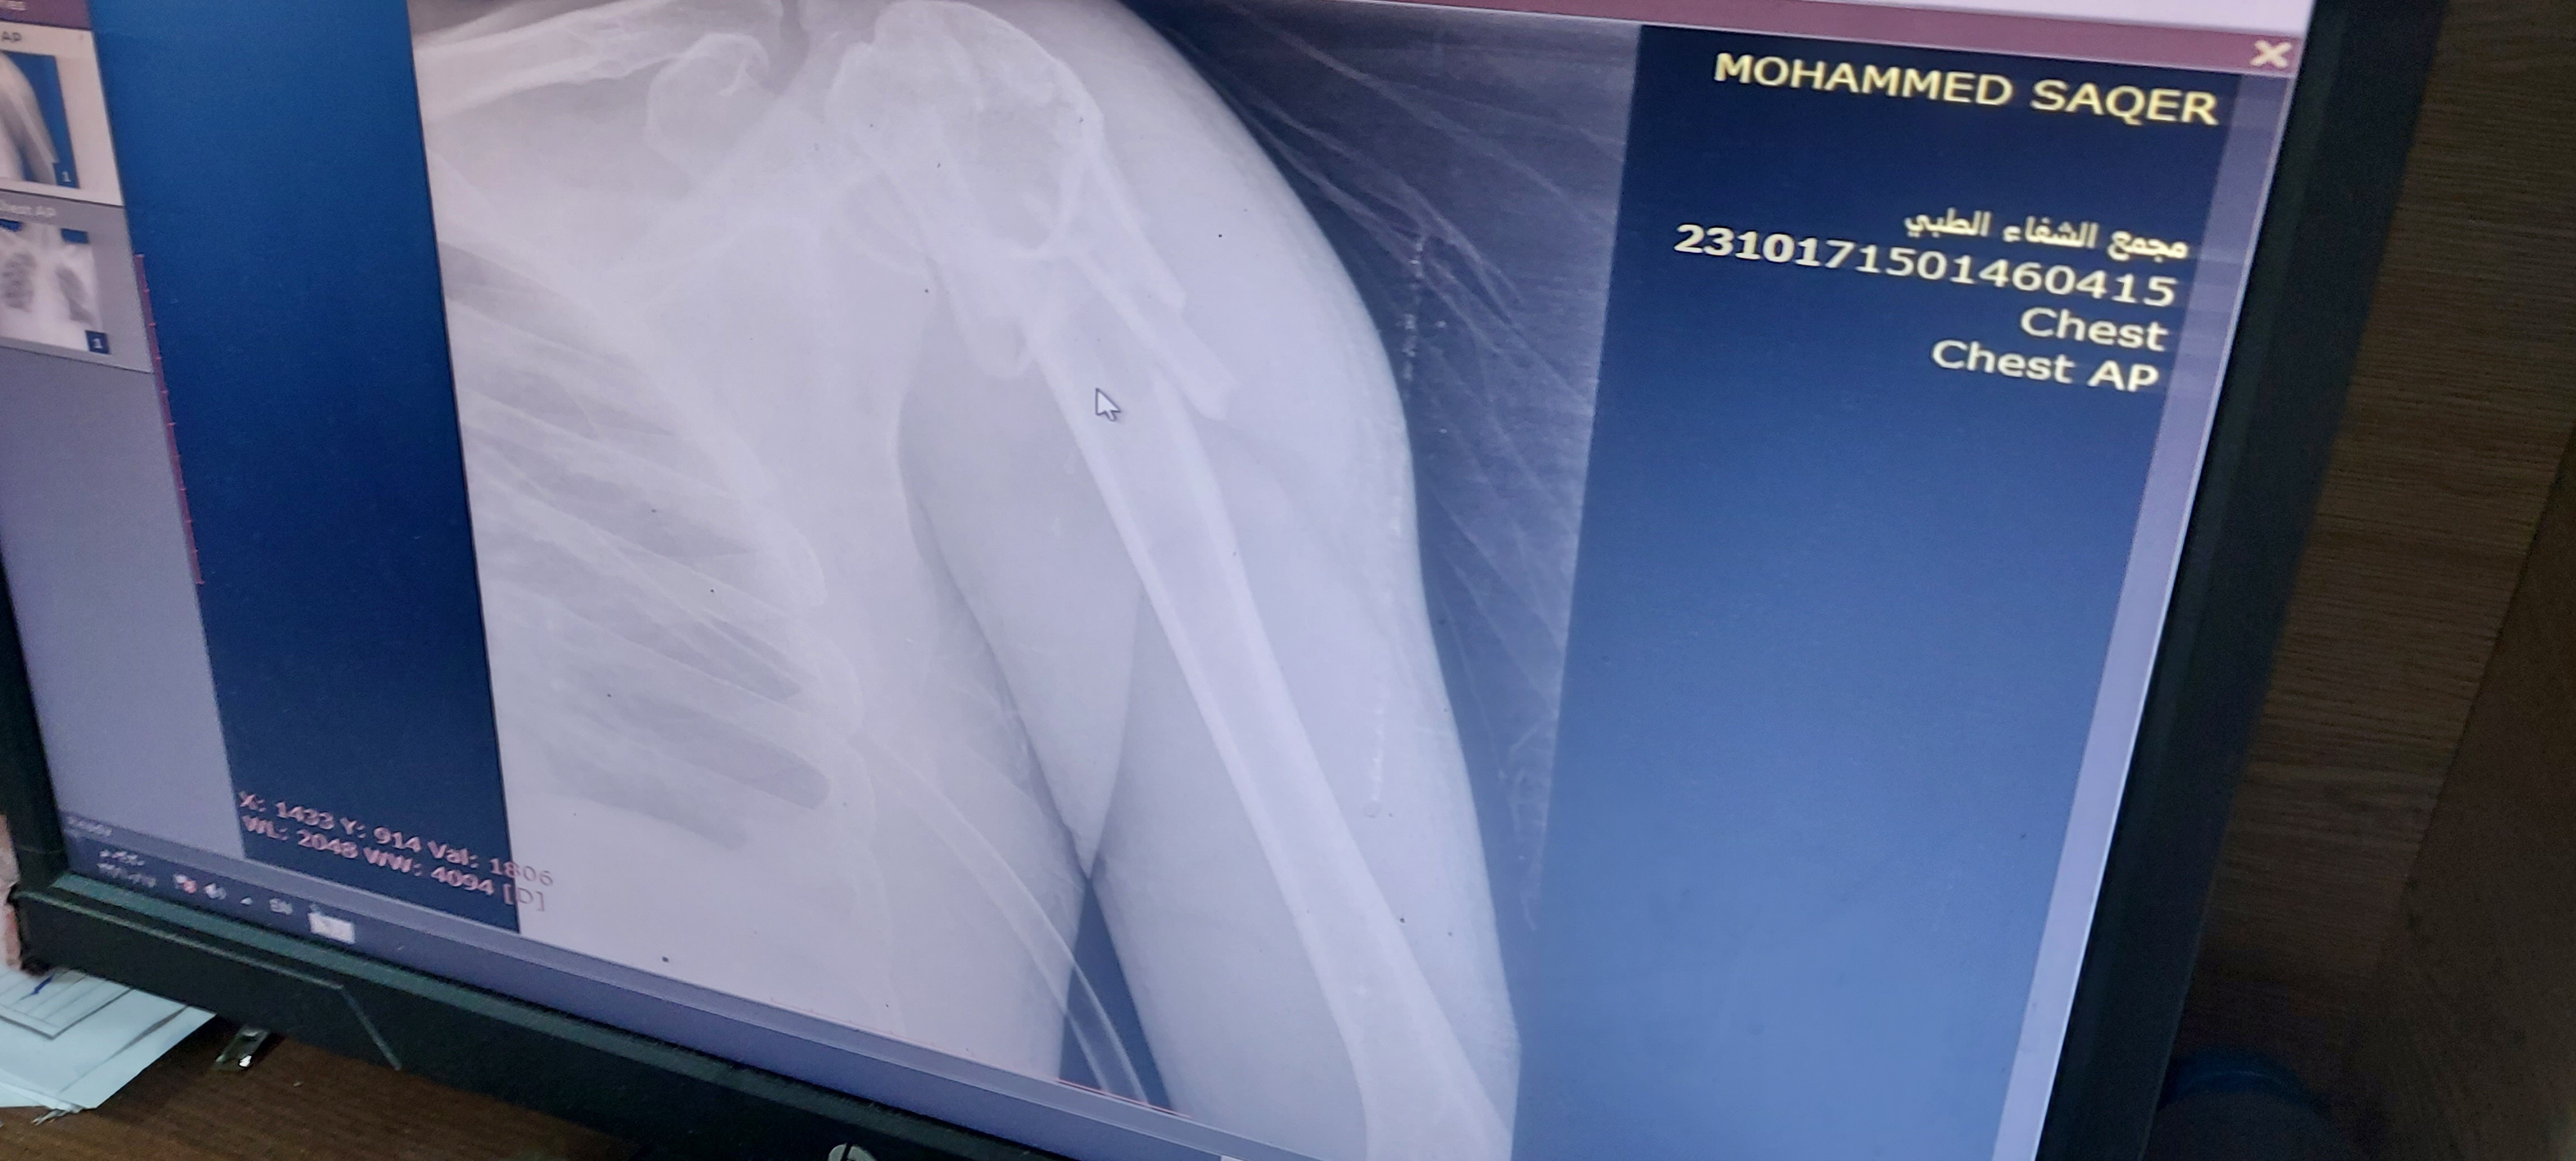

During the brutal war on Gaza, my life was forever changed . In a moment of unimaginable horror, I was caught in an Israeli airstrike that left me with severe back injuries and multiple fractures all over my body .

Since that day, I have not been able to walk again... I now rely on a wheelchair to move around . The physical pain is overwhelming, but it’s the emotional scars that cut the deepest. The dreams I once had now feel distant, buried under the rubble of destruction ️.